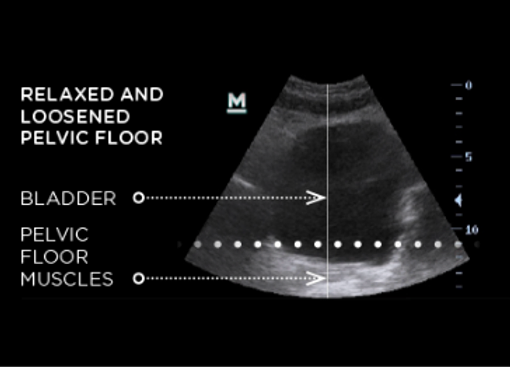

Esmella Before Ultrasound Image

This might be a result of weak pelvic floor muscles since pelvic floor muscles play an important role in supporting pelvic organs and controlling continence. Physiological changes can contribute to the development of urinary incontinence; changes such as vaginal delivery, menopause, and aging can decondition pelvic floor muscles.